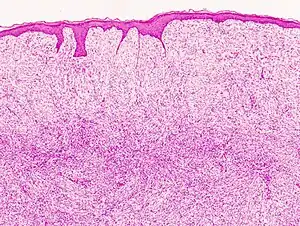

| Histopathological image of dermatofibrosarcoma protuberans. Local recurrence long after the first excision. H&E stain | |

-

Subcutaneous tissue infiltration (i.e. "honeycomb" growth pattern)

Monotonous, plexiform structure of tumour

DFSP formed both by fibroblastic and histiocytic elements

Hemosiderin deposits beneath the tumour

Immunostain positive for CD34